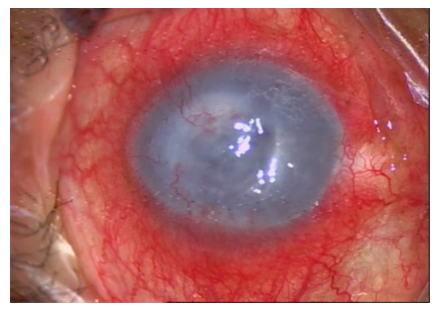

患者,男,64岁;因“左眼视力下降伴眼痛、畏光流泪2年,加重1周”于2018年12月11号于我院眼科就诊;患者20年前行左眼白内障手术、10年前双眼受伤史,有双眼高度近视病史。专科检查:右眼视力无光感,左眼视力:手动/眼前;眼压正常;左眼泪道冲洗通畅,右眼泪道冲洗大量返流,返流无脓液;左眼结膜混合充血,角膜水肿,雾状混浊(+++),颞下方角膜瓷白色混浊,见大量新生血管,中央见溃疡灶,大小约3 mm×2 mm,深度达角膜基质,余球内结构窥不清;右眼睫状充血,角膜中央透明,上方及下方角膜缘灰白色混浊,可见大量角膜云翳,前房深、清,瞳孔圆,直径约4 mm,光反射存在,晶状体缺如,玻璃体腔混浊,隐约可见晶状体位于视网膜前(图1,2 )。眼球彩超提示双眼晶状体脱位(脱位于玻璃体腔),左眼玻璃体浑浊,右眼玻璃体内可见细小带状回声;右眼角膜内皮计数为2 573个/mm2。入院诊断为“左眼角膜溃疡,左眼角膜白斑,右眼角膜云翳,双眼晶状体脱位”。

20230519162133_9564.png

图1 术前左眼图片

Figure 1 Preoperative image of the left eye